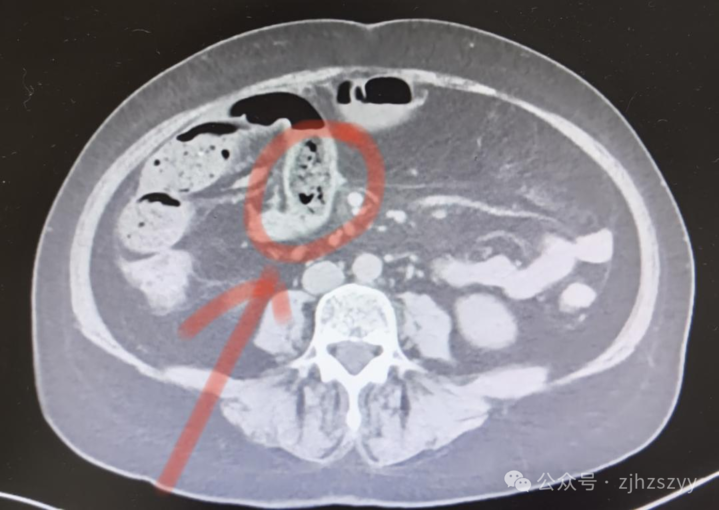

10月21日,浙江杭州58岁的宋女士一连吃了好几个柿子。没想到第二天,腹部就出现阵阵绞痛,难以忍受,到杭州市中医院检查确诊为小肠肠梗阻。在收治入院过程中,她的病情急转直下,还出现了腹腔积液。医院紧急安排手术,将一块比鸡蛋还大、坚硬如石的“柿石”取出,一周后患者顺利康复。

➤ 如果“柿石”进入肠道又无法顺利排出,则可能导致肠梗阻,严重者会引发肠坏死,甚至引起弥漫性腹膜炎而危及生命。